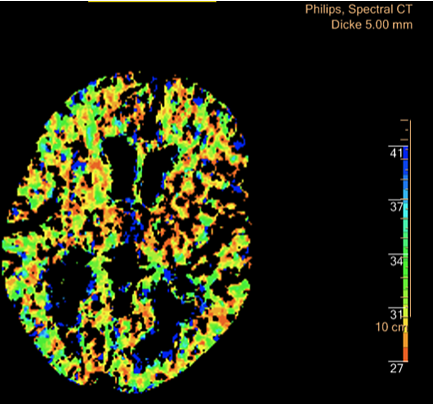

Die Bildgebungsmöglichkeiten der neuen Technik eröffnen den Ärzten "neue Dimensionen" der Diagnose (Foto: Südharz-Klinikum)

Die Künstliche Intelligenz der eingesetzten Software ermöglicht sowohl die Herabsenkung der Röntgendosis als auch der Menge des eingesetzten Kontrastmittels. Deutlich verbessern wird sich im Südharz Klinikum die Bildgebung bei Schlaganfällen durch eine Darstellbarkeit der Durchblutung (Perfusion) des gesamten Hirns im CT sowie verbesserte Optionen der Abbildung von Gefäßen des Hirns.